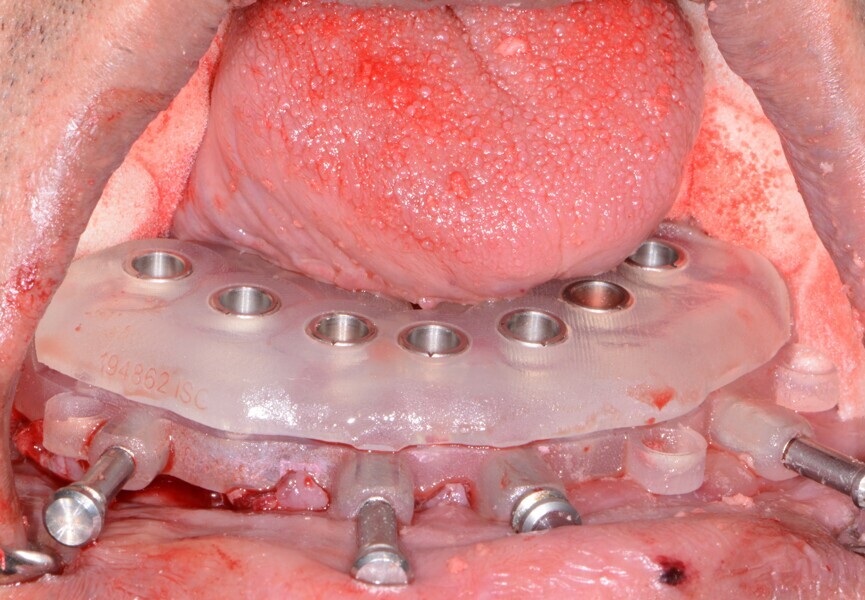

Fig. 16: Mandibular bone levelling guide.

Fig. 17: Mandibular implant surgical

guide.